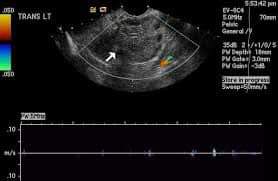

Doppler

- little or no intra-ovarian venous flow

- absent arterial flow (poor prognostic sign)

- absent or reversed diastolic flow

- normal vascularity does not exclude intermittent torsion

- normal Doppler flow can also occasionally be found due to dual supply from both the ovarian and uterine arteries (ovarian artery and a branch from the uterine artery respectively)

Left ovarian torsion with laparoscopic image